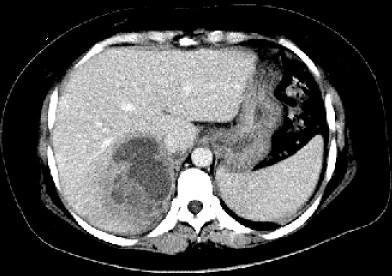

问题 女,36岁,右上腹痛,有发热,白细胞计数升高,CT检查如图,最可能诊断是 ( )

选项 A、肝黄色肉芽肿 B、肝胆管细胞癌 C、肝淋巴管瘤 D、肝脓肿 E、原发性肝癌

答案 D